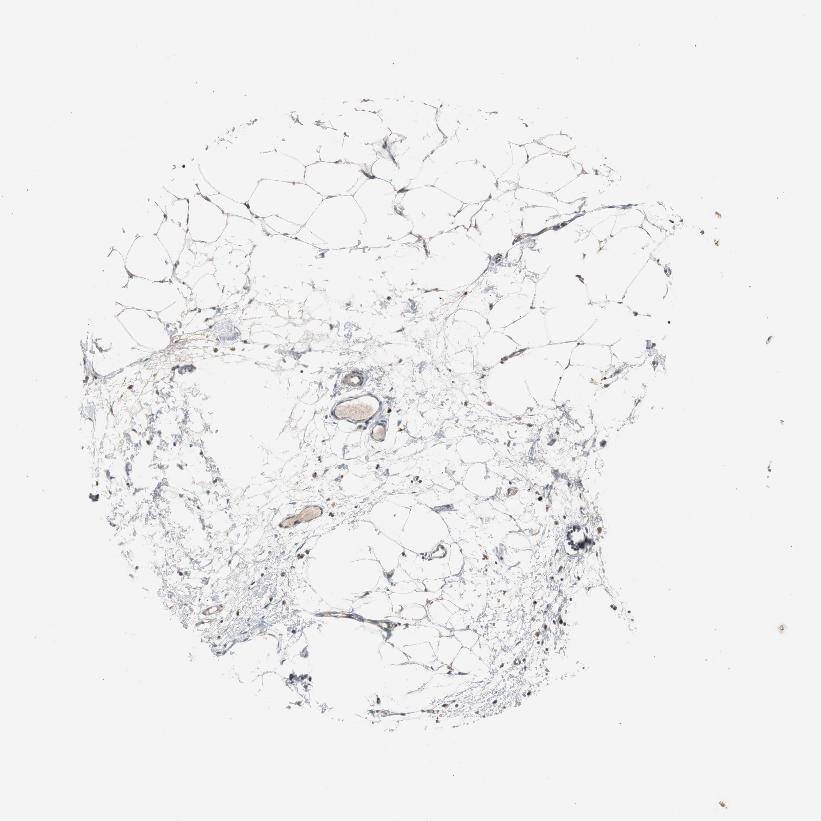

ADIPOSE TISSUE - Antibody stainingi

Antibody staining in the annotated cell types in the current human tissue is reported as not detected, low, medium, or high, based on conventional immunohistochemistry profiling in selected tissues. This score is based on the combination of the staining intensity and fraction of stained cells.

Each image is clickable and will lead to virtual microscopy that enables deeper exploration of all samples and also displays staining intensity scores, fraction scores and subcellular localization as well as patient and tissue information for each sample.

Antibody HPA006367

Adipocytes Not detected